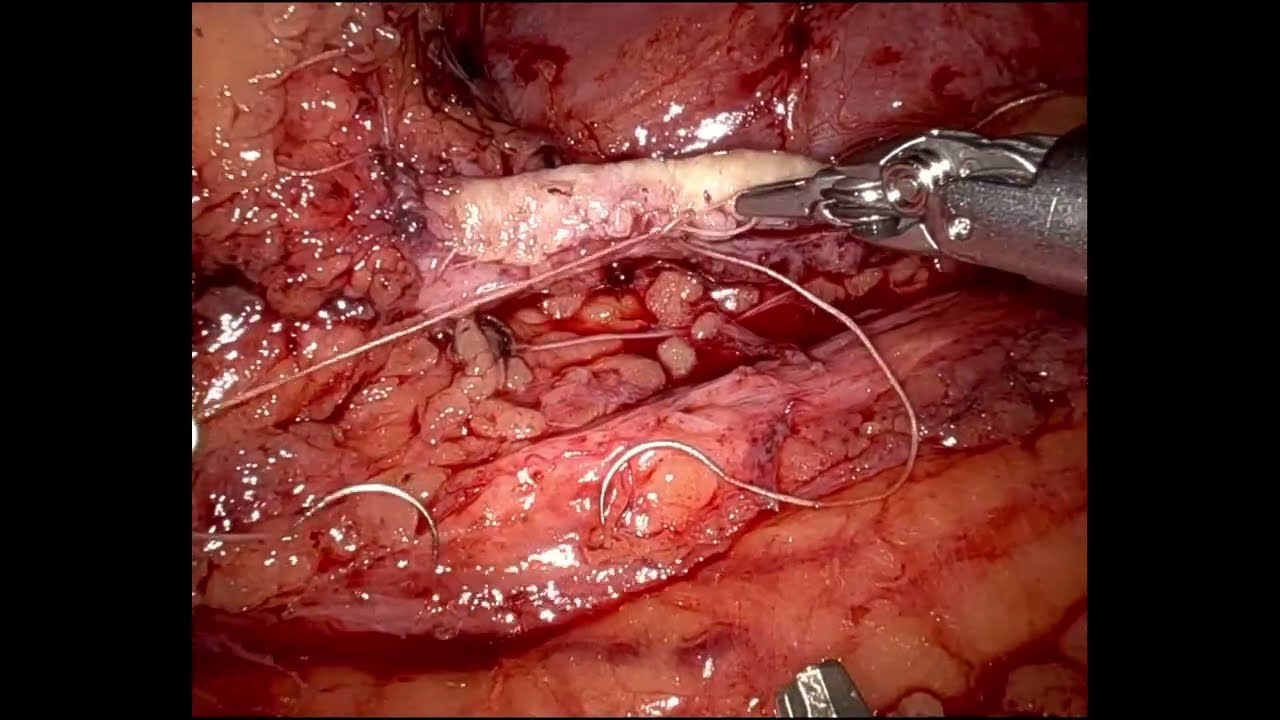

#219 Robot-assisted minimal invasive CABG using bilateral thoracic arteries- Dr. Michiel Algoet

KS Awards, Robotics, Surgeon ';